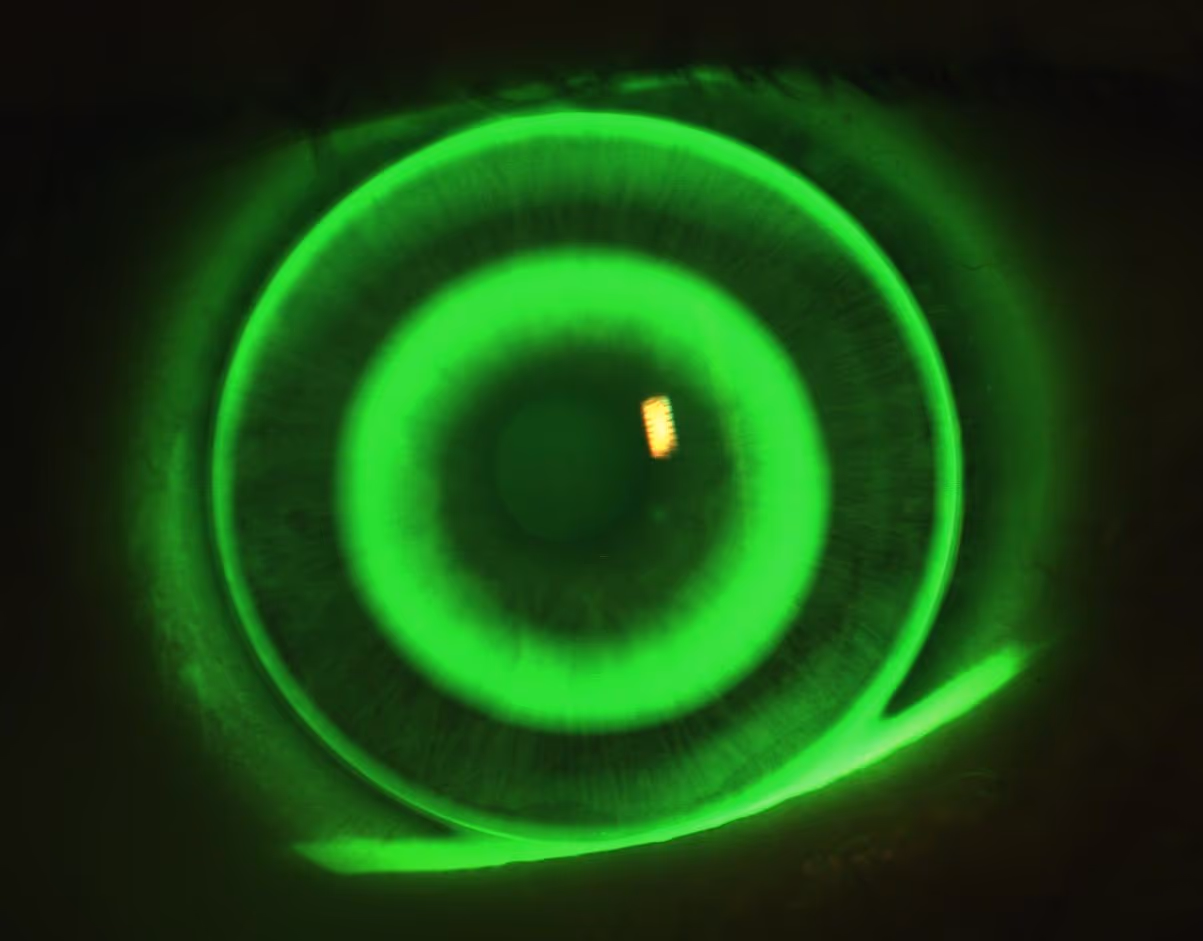

As lentes rígidas gás-permeáveis costumam ser muito úteis em pacientes com ceratocone, aumento da curvatura corneana, astigmatismo irregular e em parte dos casos após transplante de córnea. Elas criam uma superfície óptica mais regular na frente do olho, o que frequentemente melhora nitidez e contraste quando a lente gelatinosa já não entrega visão suficiente.

Em córneas mais curvas ou irregulares, como no ceratocone, a imagem pode ficar distorcida mesmo com óculos ou lente gelatinosa. A lente rígida cria uma nova superfície óptica regular na frente da córnea, e isso costuma melhorar bastante a qualidade visual.

Desenhos disponíveis: córnea, corneoescleral, piggy-back

A lente rígida gás-permeável aparece em vários desenhos. A corneana clássica fica apoiada sobre a córnea, em um diâmetro menor, e é o desenho mais usado em ceratocone leve a moderado. A corneoescleral tem um diâmetro intermediário, apoiando parte do peso na periferia da córnea e parte no limbo — costuma ser uma alternativa útil em córneas um pouco mais irregulares ou quando o conforto da corneana menor não ficou bom.

Sim. A topografia de córnea é essencial para entender a curvatura e a irregularidade antes da adaptação. Em ceratocone e córneas irregulares, ela também serve para acompanhar a doença ao longo do tempo e detectar progressão precoce, o que pode mudar a conduta (por exemplo, indicar crosslinking).